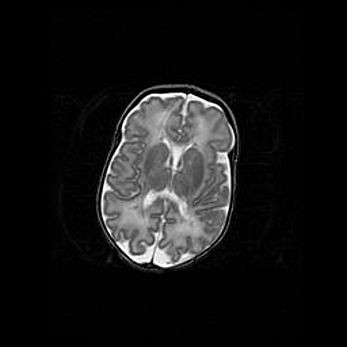

Мальформация Денди-Уокера. Киста задней черепной ямки.

Агенезия мозолистого тела.

Возраст: 2,5 месяца

Вес: 2420 г

Пол: женский

Окружность головы: 37 см

Срок гестации: 32 недели

Мальформация Денди—Уокера — редкий вид патологии ЦНС, представляющий собой врожденный порок развития каудального отдела ствола и червя мозжечка, ведущий к неполному раскрытию срединной (Мажанди) и латеральных (Лушка) апертур IV желудочка мозга. Для этогно синдрома характерна триада симптомов: гипотрофия червя мозжечка и/или полушарий мозжечка, кисты задней черепной ямки, гидроцефалия различной степени. В 70% случаев порок сочетается и с другими аномалиями головного мозга, в частности с агенезией мозолистого тела.